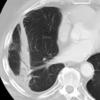

Radiation case 1

Date: 07/07/2004

Views: 3463